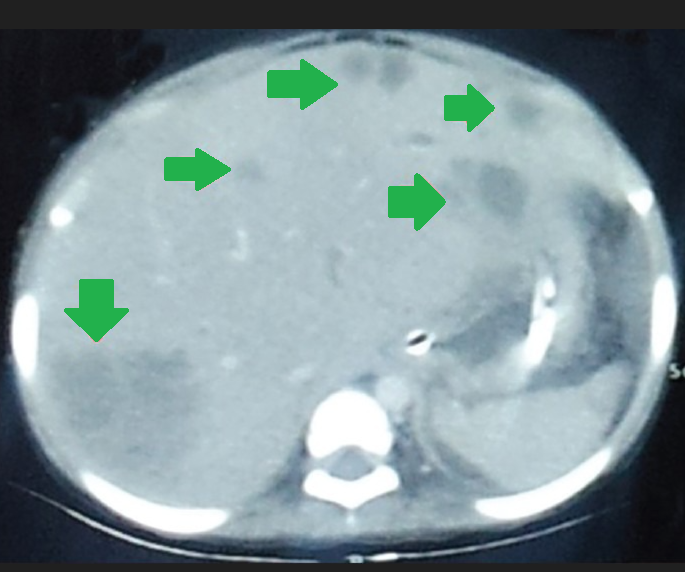

Multiple hepatic abscesses in other patients with cholecystocolic fistulas (Courtesy Dr. V. Penopoulos)